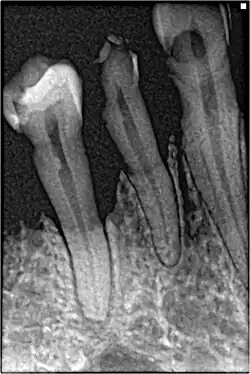

If disease is identified through this process, then a full periodontal analysis is performed, often by dental hygienists, oral health therapists, or specialist periodontists. This involves full mouth periodontal probing and taking measurements of pocket depths, clinical attachment loss and recession. Along with this other relevant parameters such as plaque, bleeding, furcation involvement and mobility are measured to gain an overall understanding of the level of disease. Radiographs may also be performed to assess alveolar bone levels and levels of destruction.[40]